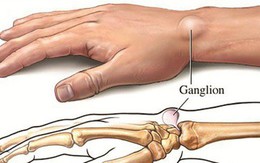

Khi bị nổi cục u không đau, đừng tự 'đoán' lành hay ác, khám chậm trễ có thể thành tật

26/12/2017 20:31

Khi bỗng nhiên mọc ra 1 cục u ở đâu đó, ví dụ như trên cổ tay. Không đau không ngứa nhưng lại lo lắng không biết lành hay ác tính, nhiều người để "kệ" nên đã phải bị tật suốt đời.